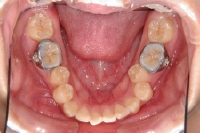

• 模型とその分析

• 上顎の内側に装置

下顎の奥歯にバンドを装着